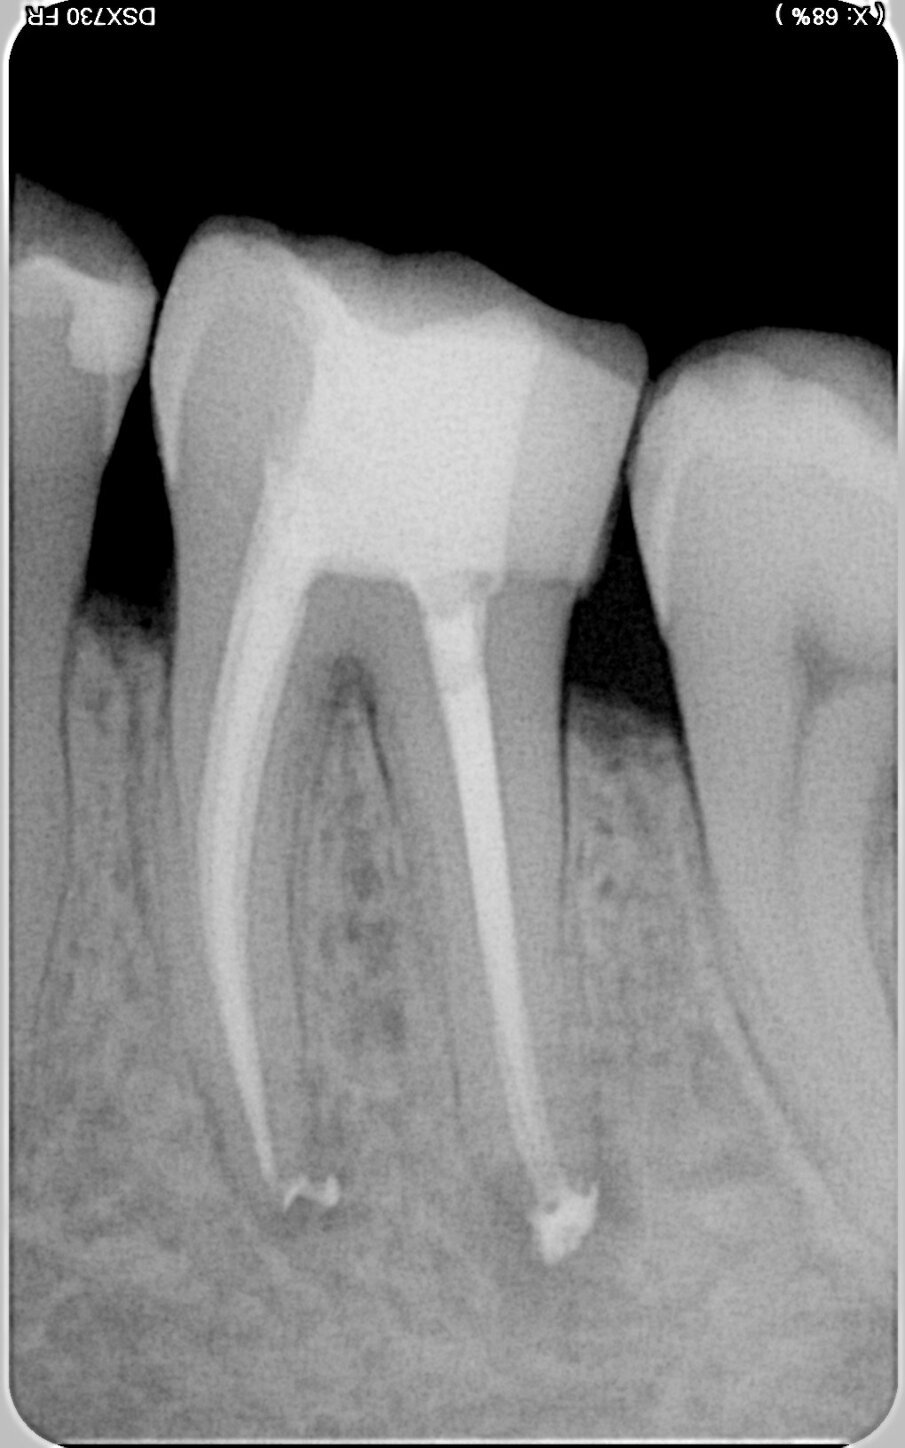

In Case 1, the appropriate access was achieved with an orifice opener. The extreme curvature in the apical third presented a particular challenge during preparation. The following sequence was therefore used: the 10/.05 HyFlex EDM file was followed by the 20/.05, and the universal file 25/~ HyFlex EDM OneFile then performed most of the work in the mesial and distal root canals. The final sequence involved the 40/.05, 50/.03 and 60/.02 files in the distal root canals for final shaping. In this process, Jeni enabled rapid preparation despite the highly curved profile of the root canals. Each file virtually worked itself to its working length. The natural shaping of the root canals is clearly shown in the postoperative radiographic image (Fig. 3).